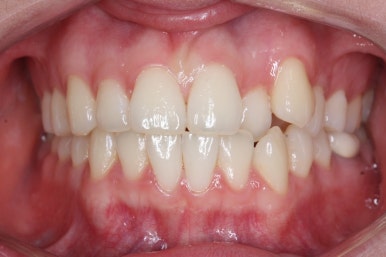

위아랫니가 매우 가지런해졌고 고민하셨던 덧니도 말끔히 개선되었습니다.

부산부정교합 키다리아저씨치과에서 이번 덧니 환자분을 치료하는데 걸린 총 기간은 14개월이였습니다.

14개월만에 치아는 가지런해졌고, 위아래 치열의 중앙도 맞아졌으며 발치를 하지 않았음에도 치열이 뻐드러지거나 돌출되지 않았습니다.

전반적으로 매우 좋아졌습니다.

또한 오히려 부각되었던 대문니의 뻐드러짐이 치료 후 개선이 되었고 웃는 모습도 굉장히 예뻐졌습니다.